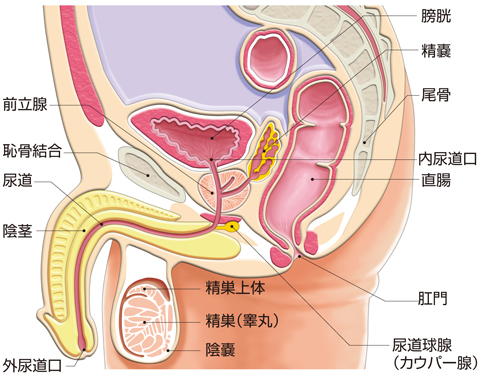

前立腺炎の場合、一般的には会陰部(肛門の前)の鈍痛、 睾丸の鈍痛、排尿痛があげられます。 そして、前立腺炎では多くの場合、この会陰部に痛みが生じます。 会陰部の痛み 急性前立腺炎の場合 急性前立腺炎の場合は、高熱と会陰部痛をともなうため、 男性 会陰部にしこり person 30代/男性 前も相談させて頂きました。 だんなが睾丸のすぐ下から肛門の間にしこりを発見しました。 去年には肛門周囲膿瘍で入院したこともあり、診察を受けに行きましたが、経過は大丈夫で、しこりについては1919 男性 男性の尿道は長く、外尿道口から入った細菌は、膀胱に達する前に排尿によって流されることが多い。前立腺からの分泌液には、細菌の侵入を防ぐ働きがある。 女性 女性は、男性に比べて、尿道が短い上、肛門や膣前庭部と外尿道口が近いので、その分、細菌が膀胱の中に入りやすい。

会陰 ( えいん )とは、 解剖学 において、狭義では 外陰部 と 肛門 の間、広義では左右の 大腿 と 臀部 で囲まれる 骨盤 の出口全体をさす。 恥骨結合 と左右の 坐骨結節 、 尾骨 を結ぶ菱形部となる。会陰と残尿感の解消には、 一体どのような関係性があるのでしょうか。 男性は蟻の門渡りを押すことで残尿感を解消できるのか? 排尿を終えた直後なのに「まだ膀胱内に尿が残っているような気がする、 なんだかスッキリしない」という不快感を覚える 男性の陰部のかゆみの原因として考えられる疾患とは? 男性の陰部にかゆみの症状があるとき、大まかな原因としては「性感染症」「皮膚疾患」の2つの場合が考えられます。 かゆみのある性感染症としては「性器ヘルペス・尖圭コンジローマ・梅毒」などがあり、どれも性行為により感染する可能性があります。 性器ヘルペスでは、陰部に水膨れができ

会陰部 広義の会陰の定義 (会陰部も参照) 前方の陰丘、外側の大腿内側面、後方の殿溝と殿間裂の上縁に挟まれた菱形の領域 (M) 狭義の会陰の定義 男性の場合尿道と会陰の間、女性の場合膣と肛門の間を指す (KH237) WordNet the general region between the anus and the男性の会陰は前後径5~6センチメートル、女性では2~3センチメートルである。 この部分の皮膚の正中線には色素に富んだ会陰縫線 (ほうせん)があり、男性では陰嚢縫線に続く。 会陰部皮下には脂肪組織、平滑筋線維が多く存在し、その深部には横紋筋からなる会陰筋層がある。 骨盤腔 (こう)を上方からみると、骨盤下口を会陰筋が筋膜、腱膜 (けんまく)とともに会陰部のヘルニアについて情報をまとめました。 ヘルニア治療辞典 男性と女性では、起こる場所が異なると言われていますが、女性の方がかかる率が高くなっています。 恐らく、女性は妊娠や出産などがあるため、会陰部が大きく収縮することが原因の1つではないかと考えられます。

生殖器の構造 看護roo カンゴルー

男性の生殖器系の構造 21 男性の健康上の問題 Msdマニュアル家庭版

生殖器系 からだのしくみを調べる 医療総合qlife